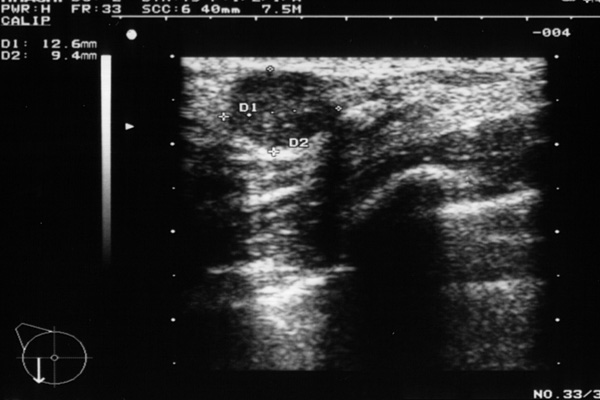

Mammasonografie bei der Patientin

In der Mammasonografie zeigt sich eine echoarme, homogene, scharf begrenzte Raumforderung in der rechten Mamma bei 9 Uhr. Sie hat eine Grösse von 1x2cm. Man sieht keinen pathologischen Schallschatten und es ist eindeutig keine Zyste.